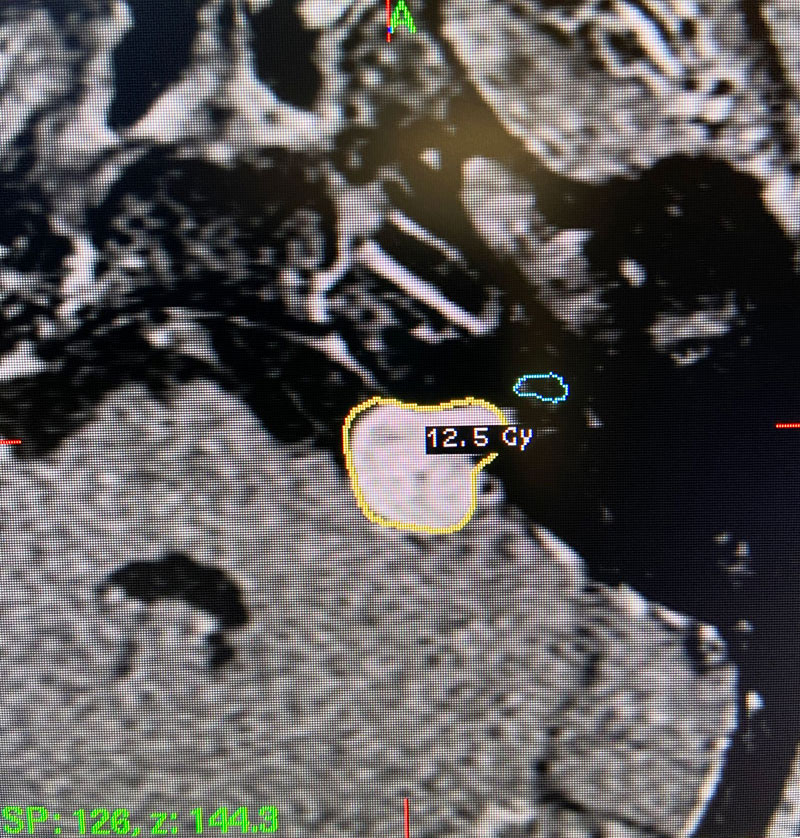

This patient: This patient had a moderate sized , symptomatic acoustic neuroma with serviceable hearing. Gamma Knife was recommended. A Gamma Knife treatment was performed by Dr. Michael Brisman. The radiation oncologist was Dr. Leester Wu. A treatment plan was made that was very conformal to the tumor. A prescription of 12.5Gy to the 50% isodose line was delivered. This plan involved a mean cochlear dose of 3.5Gy.

Image 1: Pre-operative imaging of the left acoustic neuroma.

Image 2: Intra-operative Gamma Knife treatment planning for the left acoustic neuroma. A tightly conformal treatment is set for 12.5Gy to the 50% isodose line. The cochlea has also been contoured, based off a fused image from a fine cut T2 sequence.

This is a 55 year old woman with a history of hypertension who sought attention because of one year of progressive hearing loss in the left ear. The hearing in that ear was now about 50% of normal. She also had ringing in the left ear (tinnitus). She had no problems with her right ear. Her balance was normal and she had no other complaints. Formal audiology testing confirmed hearing loss in the left ear only. MRI with and without gadolinium demonstrated a 1.3 cm solid mass in the left cerebello-pontine angle and internal auditory canal that showed homogeneous enhancement, consistent with an acoustic neuroma.